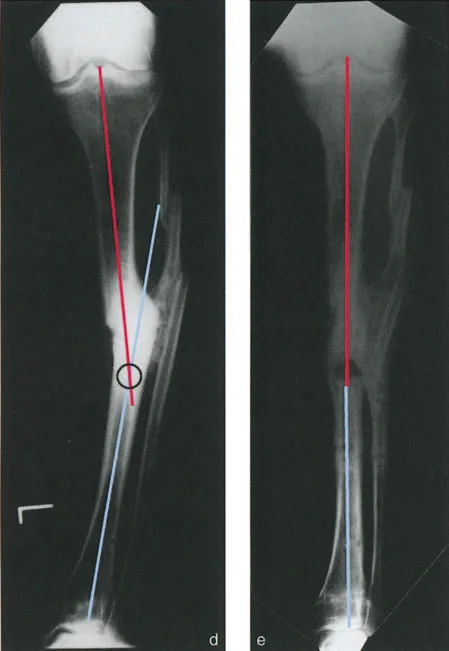

تشوهات المستوى التشريحي والمائل بزاوية أقل من 90 درجة

في هذا النوع، يمكن رؤية الانحراف والانزياح معًا في إحدى الأشعة السينية (الأمامية الخلفية أو الجانبية)، بينما يظهر في الأخرى أحد المكونين فقط (إما انحراف أو انزياح). هذا يعني أن أحد مكوني التشوه (الانحراف أو الانزياح) يقع في مستوى مائل، بينما المكون الآخر يقع في مستوى تشريحي. عندما يتم رسم هذه المستويات بيانيًا، تكون مختلفة ولكن بزاوية أقل من 90 درجة.

مثال: التئام خاطئ لعظم الساق الأيسر حيث يظهر الانحراف والانزياح في الأشعة السينية الأمامية الخلفية (AP)، بينما يظهر الانزياح فقط في الأشعة السينية الجانبية (LAT). أو قد يظهر الانحراف فقط في LAT.

في هذه الحالات، إذا كان الانحراف هو المكون التشريحي، فإن مركز دوران الانحراف (CORA) سيظهر إما قريبًا أو بعيدًا عن الالتئام الخاطئ في الأشعة السينية الأمامية الخلفية (AP) أو الجانبية (LAT). أما إذا كان الانحراف هو المكون المائل، فسيظهر مركز دوران الانحراف (CORA) قريبًا أو بعيدًا عن الكسر في المنظر الذي يظهر أقصى انزياح، وعند مستوى الكسر في المنظر الذي لا يظهر فيه انزياح.

التصوير الشعاعي بالأشعة السينية

تُعد الأشعة السينية (X-rays) الأداة الأساسية لتشخيص تشوهات العظام. يتم أخذ صور متعددة للطرف المصاب من زوايا مختلفة (الأمامية الخلفية، الجانبية، والمائلة) لتقييم التشوه في جميع المستويات. الأستاذ الدكتور محمد هطيف يولي اهتمامًا خاصًا لجودة هذه الصور ودقتها، حيث إنها الأساس الذي يُبنى عليه التحليل البيوميكانيكي.

تحليل CORA لتحديد مركز الدوران الفعلي

يُعد تحليل مركز دوران الانحراف (CORA - Center of Rotation of Angulation) حجر الزاوية في التخطيط الجراحي لتصحيح تشوهات العظام. يتطلب هذا التحليل فهمًا عميقًا للبيوميكانيكا العظمية وخبرة كبيرة، وهو ما يتميز به الأستاذ الدكتور محمد هطيف.

- ما هو CORA؟ هو النقطة الافتراضية التي يدور حولها الجزء البعيد من العظم بالنسبة للجزء القريب لتصحيح الانحراف.

- كيف يتم تحديده؟ يتم تحديد CORA برسم خطوط محورية على الأشعة السينية (AP و LAT) لكل جزء من العظم المشوه (القريب والبعيد). نقطة تقاطع هذه الخطوط هي CORA.

- أهميته: تحديد CORA بدقة يُمكّن الجراح من تخطيط قطع العظم (Osteotomy) في الموقع الأمثل. إذا تم إجراء قطع العظم عند مستوى CORA، يمكن تصحيح الانحراف بحركة زاويّة واحدة دون إحداث انزياح جديد أو زيادة الانزياح الموجود. هذا يقلل من تعقيد الجراحة ويحسن النتائج الوظيفية.